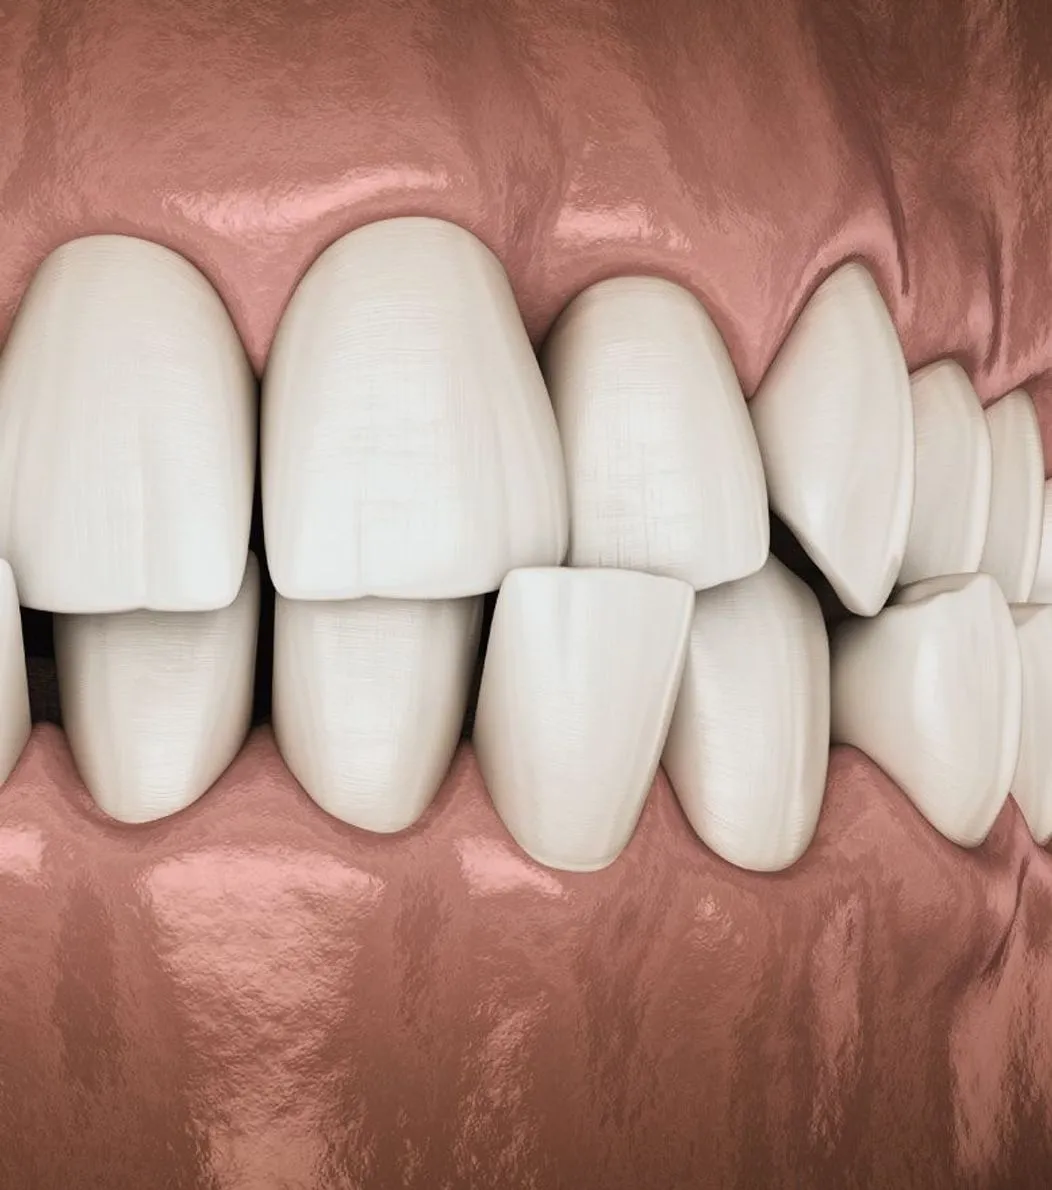

Dental implants provide a permanent, natural-looking solution for missing teeth. The implant is surgically placed in the jawbone, where it fuses with the bone for a secure and long-lasting fit. Implants help maintain bone density, restore function, and enhance aesthetics. With proper care, they can last a lifetime.